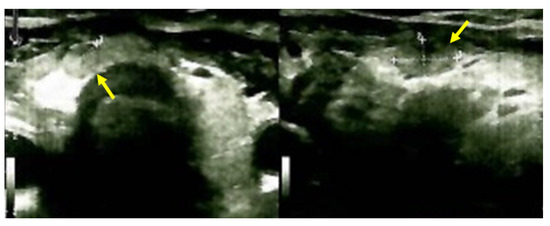

Moreover, an abdominal CT confirmed the bilateral polycystic features of the kidneys (with a convex contour due to multiple cystic lesions that were located in and protruding from the renal cortex; the posterior part of the right kidney contained the largest cyst of 6.27 by 5.36 by 6.01 cm with mass effect on the phyllo-caliceal system and protruding from the kidney). Of note, renal microlithiasis was co-present in both kidneys (Figure 8).

Figure 8.

Intravenous contrast abdominal CT showing: (A) both kidneys with multiple cystic lesions both located in and protruding from the renal cortex bilaterally, the posterior part of the right kidney with a cyst of 6.27 by 5.36 by 6.01 cm with mass effect on the phyllo-caliceal system and protruding from the kidney (the yellow arrows show cystic kidney disease) and (B) bilateral renal microstones in primary hyperparathyroidism in yellow (axial plane).